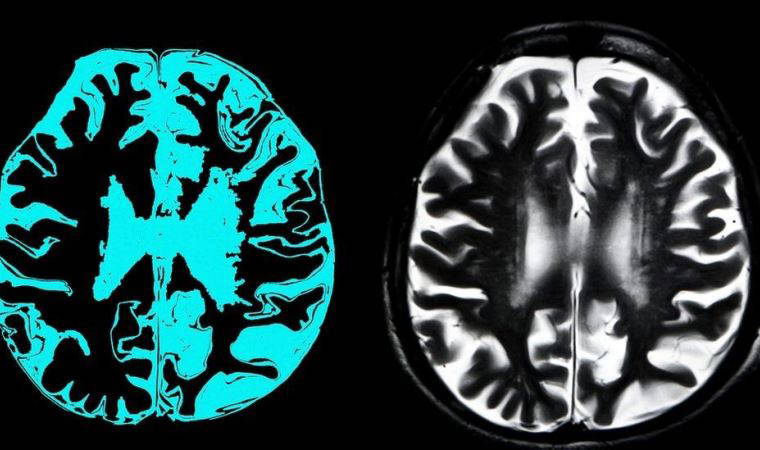

EMA kararını erken seviye Alzheimer hastası olan 3 bin kişiyle yapılan iki deneyin sonuçlarına dayandırdı. Deneyler, hastalarda ilacın düşük ve yüksek dozda verilmesinin etkilerini tespit etmek için yapıldı ve hastaların bir kısmına plasebo, yani içinde aktif ilaç maddesi içermeyen haplar verildi.

EMA, "Deneylerin sonuçları çelişkiliydi ve aducanumab ilacının erken seviye Alzheimer hastalarında etkili olmadığı ortaya çıktı. Üstelik hastaların beyin taramalarında şişkinlik ve kanama olduğu gözlemlendi. İlaç zararlı olabilir" açıklamasını yaptı.